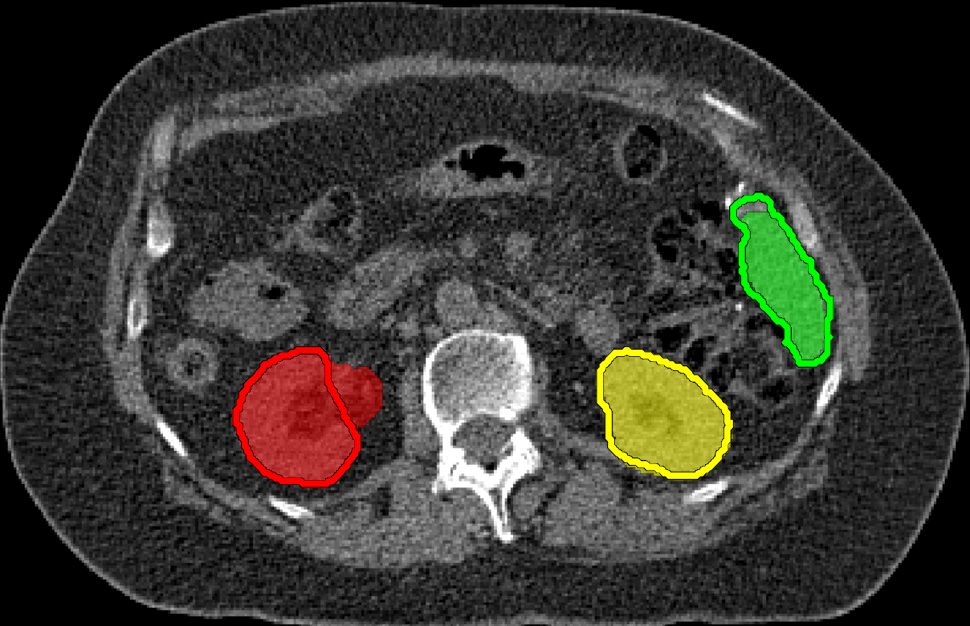

Distinct intensity appearances and smooth contrast-aligned boundaries are standard segmentation cues. However, in most real applications of image segmentation there are multiple objects of interest with similar or overlapping color appearances. Intensity edges also could be cluttered or weak. These common practical problems require additional regularization, as illustrated in the second row of Figure 1.

| two examples of images with seeds (medical and photo) | |

| multi-object segmentation using Potts model | |

| multi-object segmentation adding our hedgehog shapes prior | |

We observe that similarity between object appearances and edge clutter are particularly problematic in larger multi-label segmentation problems, e.g. in medical imaging. Our multi-hedgehog prior is fairly flexible, has efficient optimizers, and shows significant potential in resolving very common ambiguities in multi-label segmentation problems, see Fig.1 (last row). Our general multi-object segmentation framework allows to enforce “hedgehog” shape prior for any of the objects. The class of all possible hedgehog priors is sufficiently representative yet each specific hedgehog constraint offers sufficient regularization to address color overlap and weak/cluttered edges. One extreme case of our prior is closely related to the standard star shape prior [25]. The other extreme case allows shapes with restricted skeletons [18, 24].